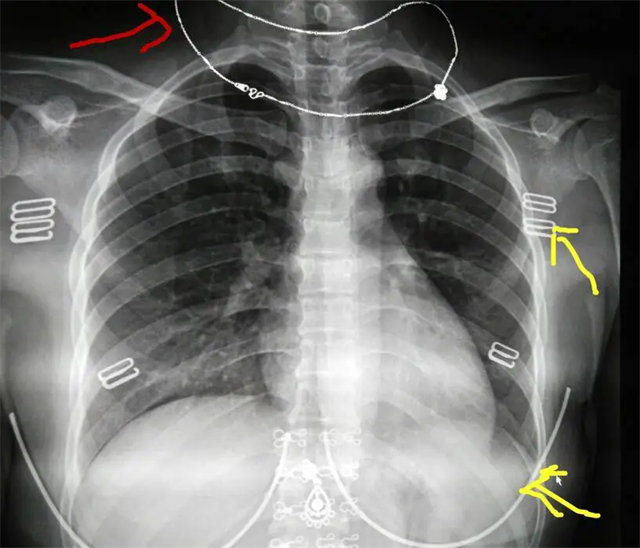

拍攝的不合格胸片的缺陷和解決方法

缺陷:雙側(cè)胸鎖關(guān)節(jié)不對稱,且有手機顯影。

解決:去除手機后,使患者左側(cè)緊貼成像件曝光。